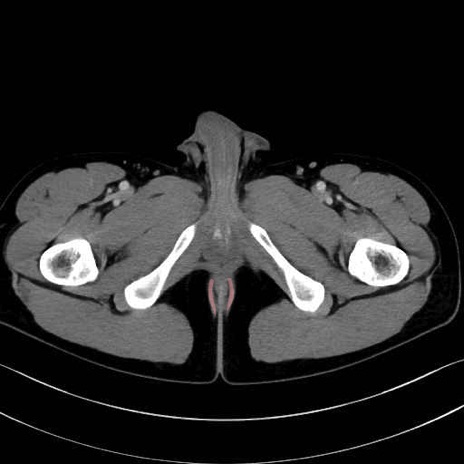

肛門挙筋 (Levator ani)